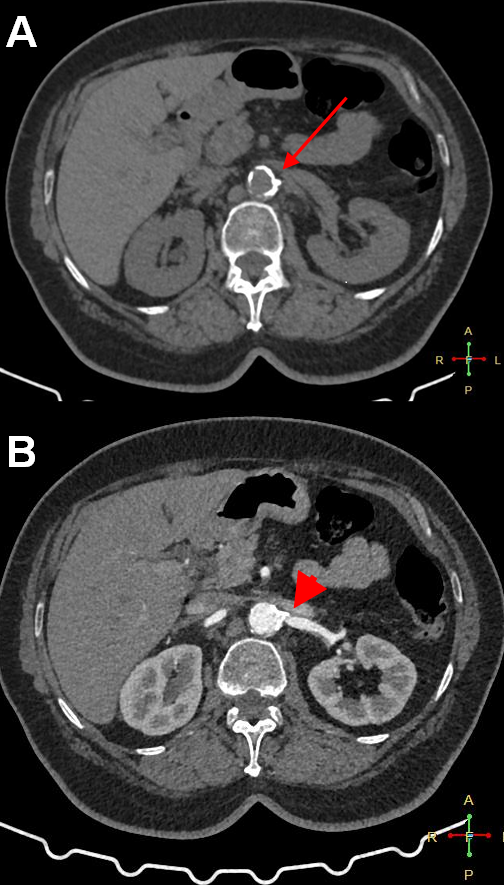

A 63-year-old woman with uncontrolled hypertension despite taking 5 antihypertensive medications was referred for percutaneous renal artery intervention. Duplex ultrasonography had shown critical left renal artery stenosis (RAS), and computed tomography angiography confirmed the presence of a tight, heavily calcified ostioproximal left RAS, as well as circumferential calcification of the abdominal aorta adjacent to the left renal artery take-off (Figure 1).